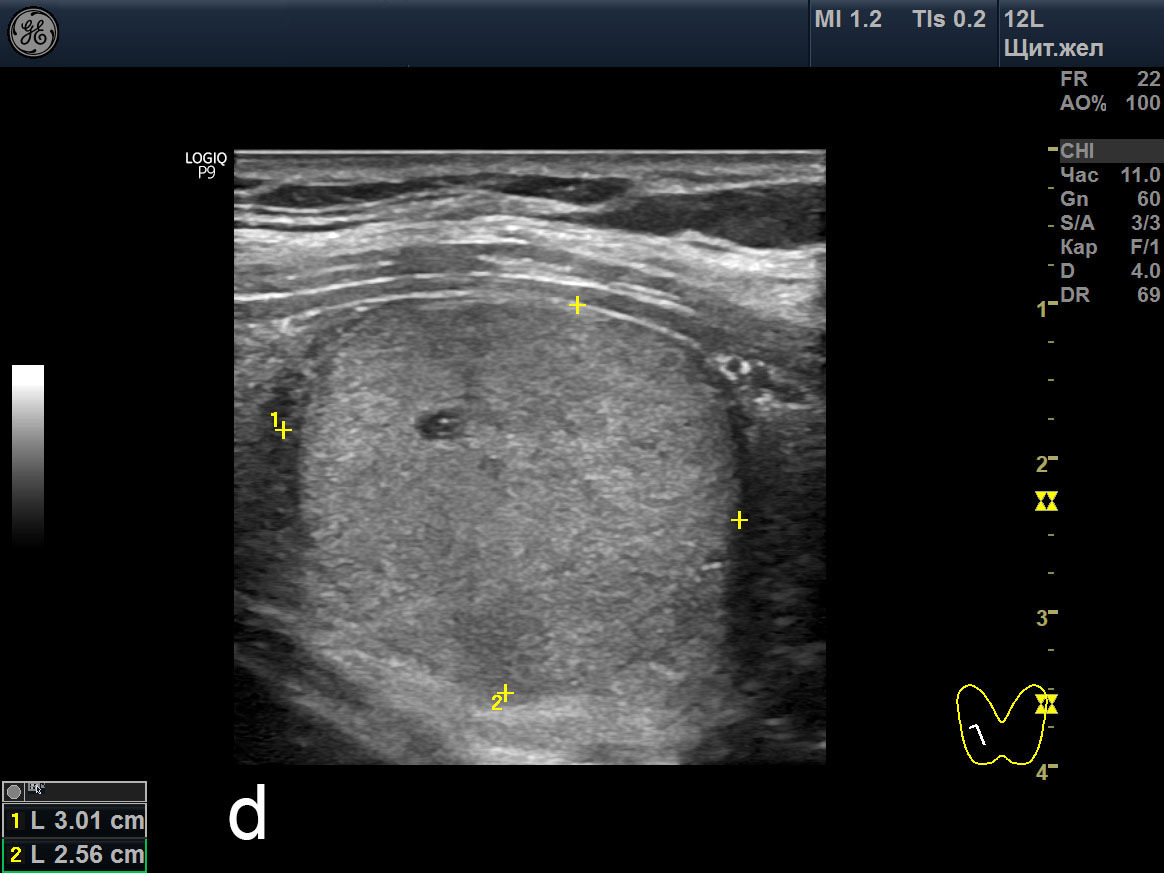

Теплый узел щитовидной

Теплый узел щитовидной 107 фотографий